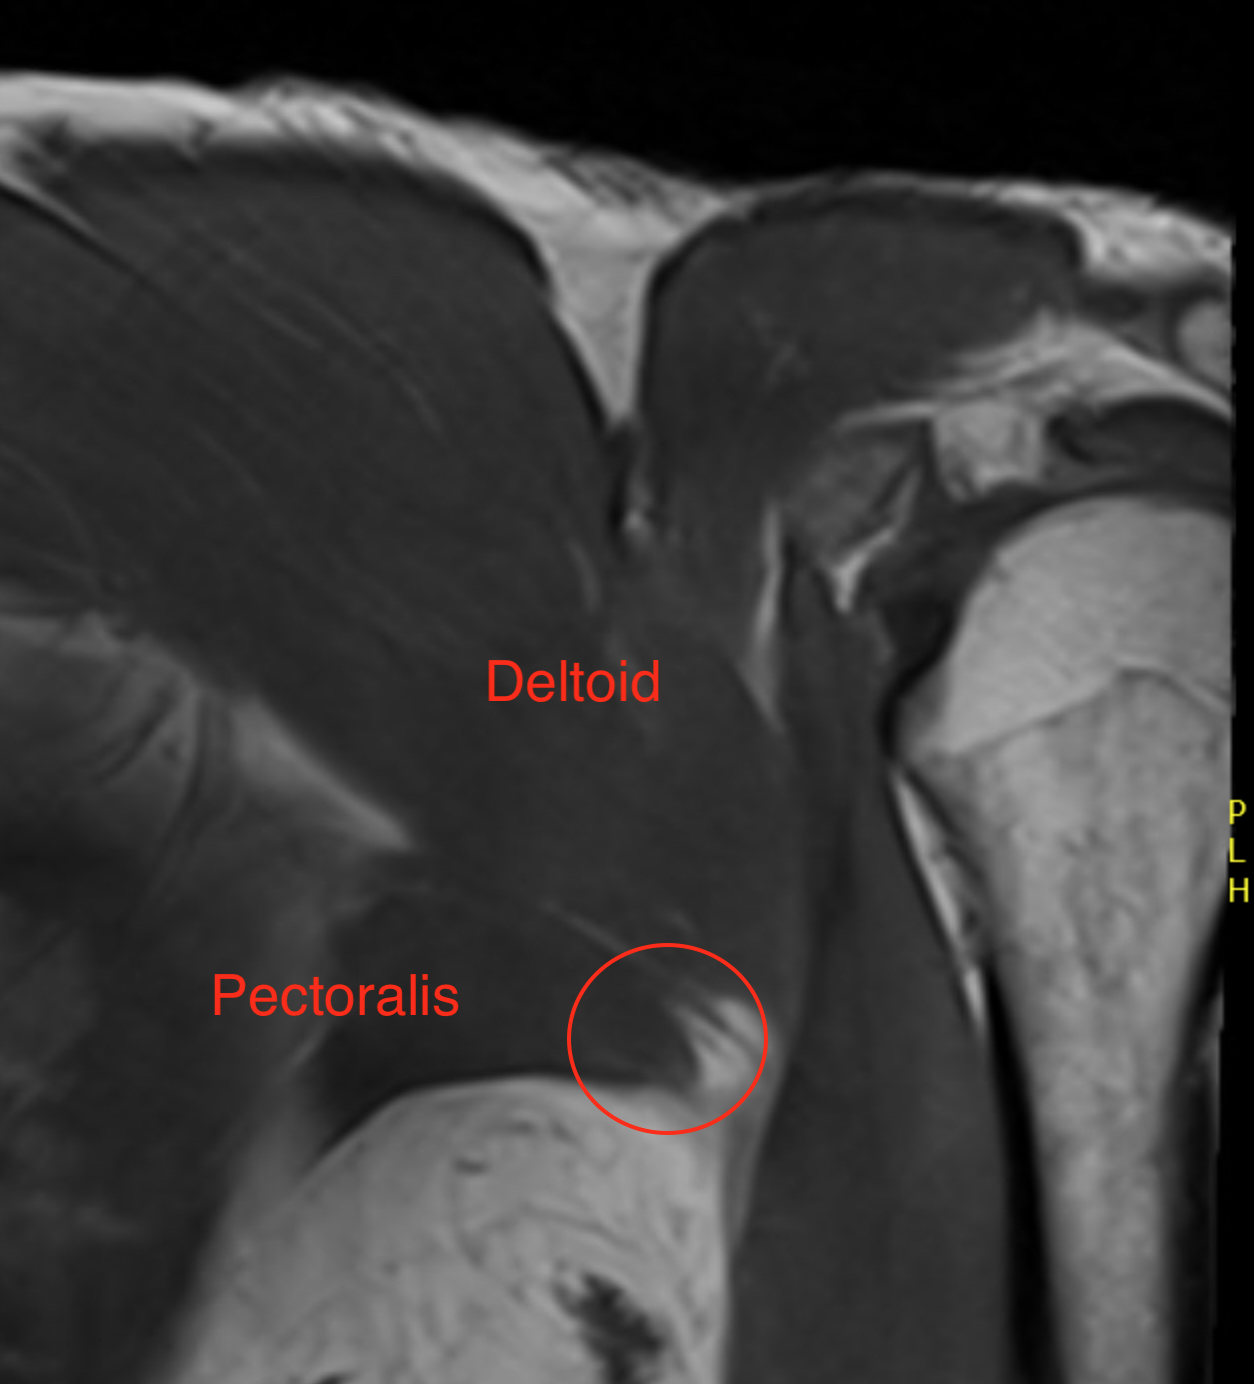

Coronal T2 MRI Right shoulder demonstrating musculotendinous avulsion